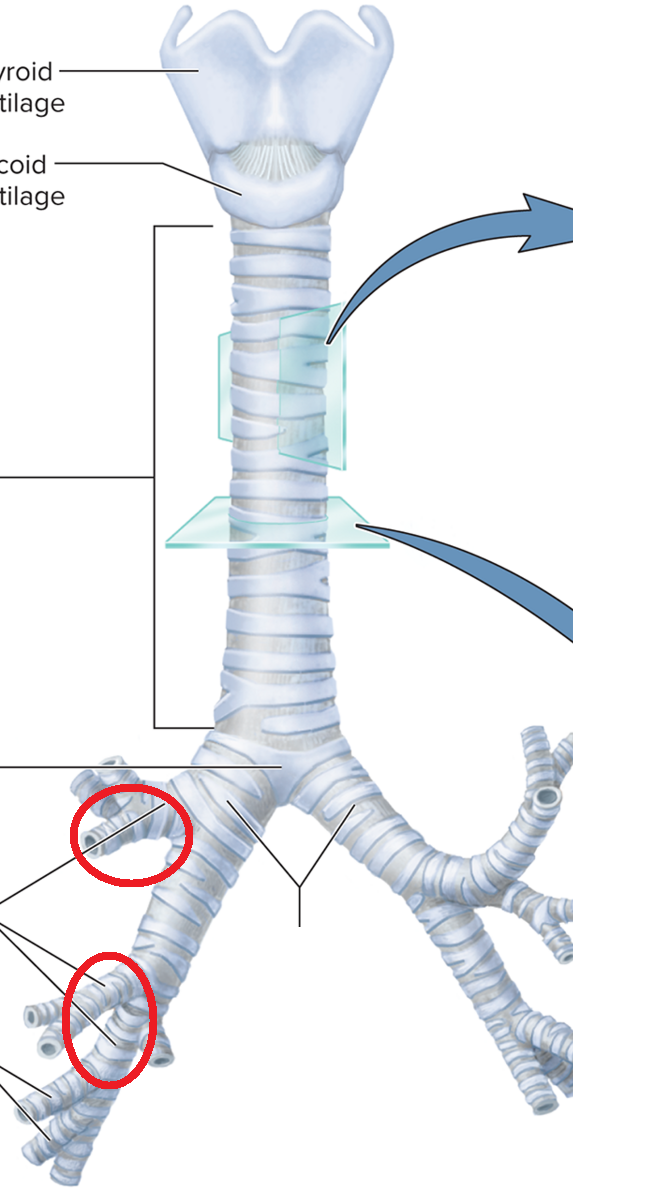

Trachea and Bronchial Tree

Main bronchi BT

Lobar bronchi BT

Segmental bronchi BT

Bronchiole BT

Terminal bronchiole BT